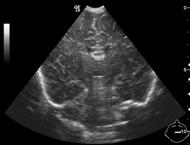

18. 5. Abdominal masses

Neuroblastoma. is a tumor that develops at any part of the sympathetic nervous system. Therefore, in over 90% of the cases the urinary catecholamine levels are elevated. It is the most frequent extra cranial, solid tumor in children and has its highest malignancy rate within the first year. It is most common in children aged 1-5 years, appears as a palpable abdominal mass, with fever, hypertension, and anemia; in cases of bone metastases, bone pain and limping are common. US examination reveals a well circumscribed, echogenic mass usually crossing the midline, dislocating the kidney; it is frequently calcified, highly vascular, surrounding and compressing the abdominal vessels. In progressive cases liver and nodal metastases can be found. The tumor can also be solid, homogenous and with a smooth margin. The adrenal region in newborns is well visualizeable with US, but at older ages only major lesions can be depicted. CT/MRI examination: can depict a large sized, irregular shaped, extrarenal mass, with frequent necrosis, hemorrhage and calcifications. The lesions show a heterogeneous contrast enhancement.

25. US examination, longitudinal view. Above the right kidney, in the adrenal region a solid, slightly inhomogeneous mass can be seen. Neuroblastoma.